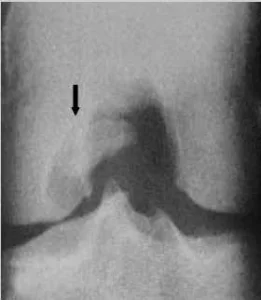

O local mais comumente afetado é a face posterolateral do côndilo femoral medial (75%) (figura 1), zona de carga (onde há transmissão de peso) dos côndilos femoral medial e lateral (20%) e superfície patelar (5%).

Exame radiográfico da localização clássica da OCD na face posterolateral do côndilo femoral medial.

(A) Incidência anteroposterior.

(B) Incidência de perfil.

(C) Incidência posteroanterior (túnel).